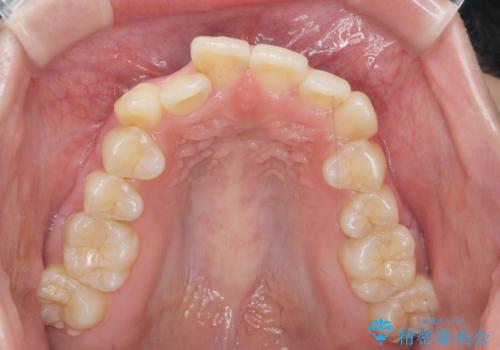

前歯のがたつきをマウスピース矯正できれいに!

- 目立つ前歯のがたつきを改善したい、と矯正治療を希望され来院されました。

今回の治療ではシミュレーションでしっかりと検討した結果、下顎は前歯を1本抜去し仕上げる治療計画としました。